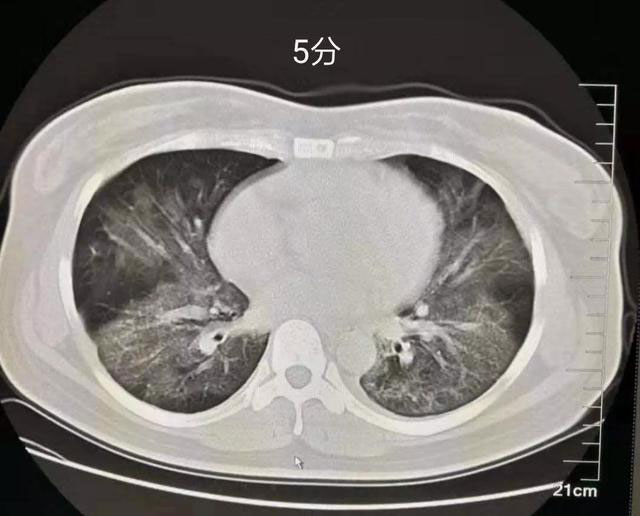

5分:双肺胸膜下区多发斑片状磨玻璃密度影,边界清楚,可短期(几天内)演变为大片实变或者逐渐吸收、纤维化,强烈提示新型冠状病毒感染性肺炎。

临床意义:无论核酸检测是否阳性,依照2019新型冠状病毒(2019-nCoV)感染肺炎治疗,传染病病房隔离。亲密接触者隔离观察。

下图为评分图解